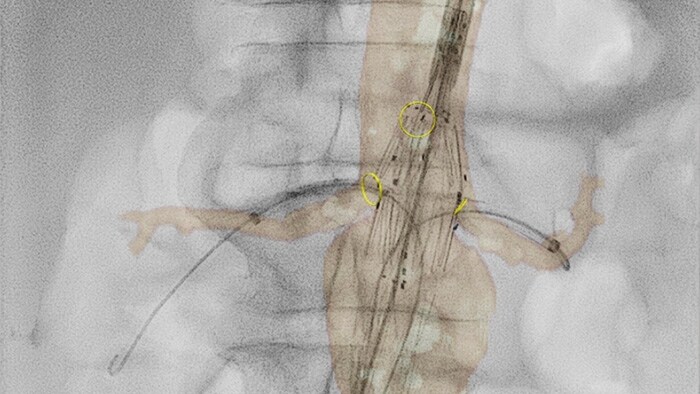

O VesselNavigator fornece um roteiro 3D intuitivo e contínuo baseado nos conjuntos de dados de CTA e ARM existentes para guiá-lo ao longo da vasculatura durante procedimentos aórticos. Um estudo1 mostrou uma redução de contraste média de 170 ml durante o reparo endovascular de aneurismas aórticos complexos com o uso das orientações de fusão de imagem de CTA do VesselNavigator.2 Outro estudo mostrou uma redução da duração média de procedimentos FEVAR/BEVAR de 6,3 para 5,2 (1,1) horas com as orientações de fusão de imagem de CTA do VesselNavigator.3

O ultrassom intravascular (IVUS) é uma tecnologia de diagnóstico por imagem baseada em cateter que permite que os médicos visualizem vasos sanguíneos de dentro para fora para ajudar na avaliação da presença e extensão de doenças. O IVUS ajuda a decidir, orientar e confirmar o tratamento intervencionista certo para cada paciente.

Visualiza imagens de vasos de alta definição com detalhes vasculares excepcionais, como apoio a estratégias precisas de tratamento, navegação e acompanhamento.